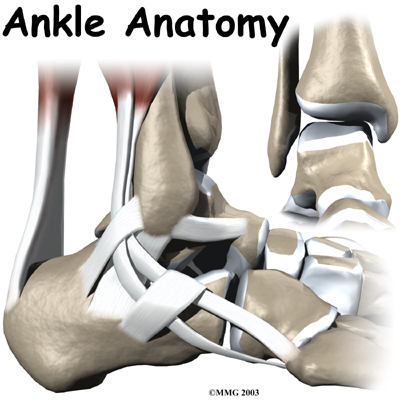

The ankle joint acts like a hinge. But it's much more than a simple hinge joint. The ankle is actually made up of several important structures. The unique design of the ankle makes it a very stable joint. This joint has to be stable in order to withstand 1.5 times your body weight when you walk and up to eight times your body weight when you run.

Important Structures

The important structures of the ankle can be divided into several categories. These include

- bones and joints

- ligaments and tendons

Bones and Joints

The ankle joint is formed by the connection of three bones. The ankle bone is called the

talus. The top of the talus fits inside a socket that is formed by the lower end of the

tibia (shinbone) and the

fibula (the small bone of the lower leg). The bottom of the talus sits on the heelbone, called the

calcaneus.

Inside the joint, the bones are covered with a slick material called articular cartilage. Articular cartilage is the material that allows the bones to move smoothly against one another in the joints of the body.

The lining is about one-quarter of an inch thick in most joints that carry body weight, such as the ankle, hip, or knee. It is soft enough to allow for shock absorption but tough enough to last a lifetime, as long as it is not injured.

Ligaments and Tendons

Ligaments are the soft tissues that attach bones to bones. Ligaments are very similar to

tendons. The difference is that tendons attach muscles to bones. Both of these structures are made up of small fibers of a material called . The collagen fibers are bundled together to form a rope-like structure. Ligaments and tendons come in many different sizes and like rope, are made up of many smaller fibers. Thickness of the ligament or tendon determines its strength.

Ligaments on both sides of the ankle joint help hold the bones together. make up the lateral ligament complex on the side of the ankle farthest from the other ankle. (Lateral means further away from the center of the body.) These include the anterior talofibular ligament (ATFL), the calcaneofibular ligament(CFL), and the posterior talofibular ligament (PTFL). A thick ligament, called the deltoid ligament, supports the medial ankle (the side closest to your other ankle).

Ligaments also support the lower end of the leg where it forms a hinge for the ankle. This series of ligaments supports the ankle syndesmosis, the part of the ankle where the bottom end of the fibula meets the tibia. support this area. The ligament crossing just above the front of the ankle and connecting the tibia to the fibula is called the anterior inferior tibiofibular ligament (AITFL). The posterior fibular ligaments attach across the back of the tibia and fibula. These ligaments include the posterior inferior tibiofibular ligament (PITFL) and the transverse ligament. The interosseous ligament lies between the tibia and fibula. (Interosseous means between bones.) The interosseus ligament is a long sheet of connective tissue that connects the entire length of the tibia and fibula, from the knee to the ankle.

The ligaments that surround the ankle joint help form part of the . A joint capsule is a watertight sac that forms around all joints. It is made up of the ligaments around the joint and the soft tissues between the ligaments that fill in the gaps and form the sac.